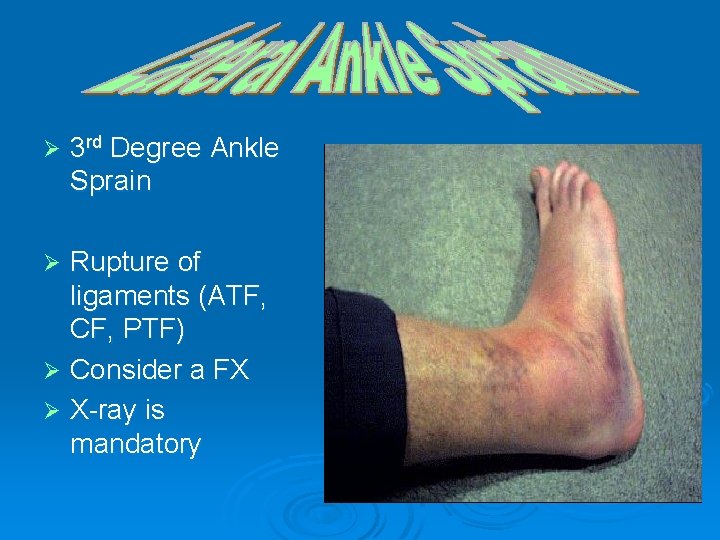

Ø 3 rd Degree Ankle Sprain Rupture of ligaments (ATF, CF, PTF) Ø Consider a FX Ø X-ray is mandatory Ø

Ø S/S Ø 3 rd Degree l Felt or heard pop l Extreme pain l Extreme/rapid swelling l No ROM l Unable to FWB